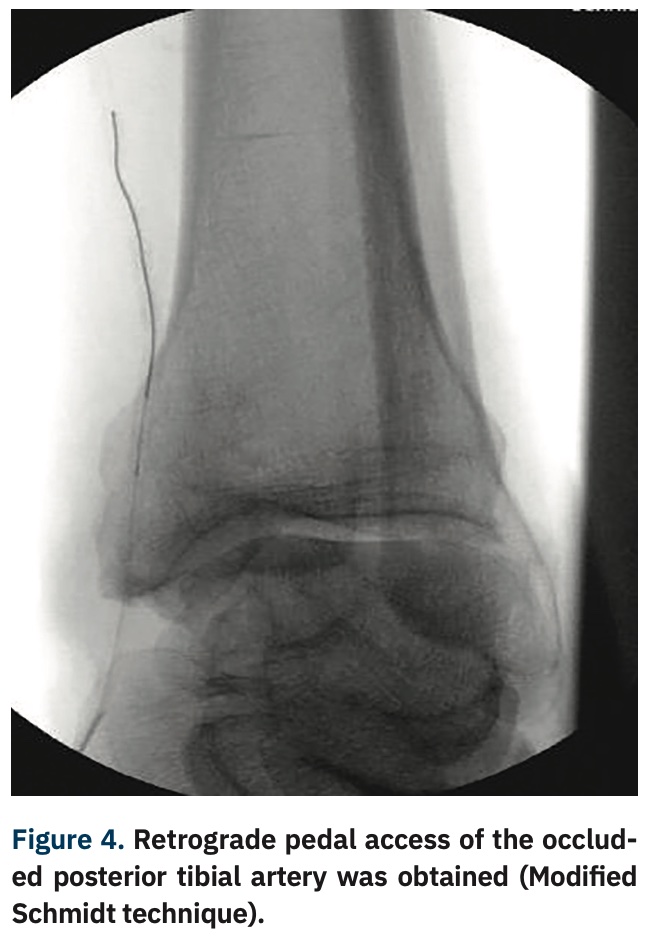

TCTAP C180 Reverse CART Technique in Above Knee Peripheral CTO Cart And Reverse Cart Technique Stent reverse cart entails creation of an open target for retrograde guidewire navigation when a stent is. The “stent reverse cart” technique involves deploying a stent within the antegrade dissected plane to create an open target for retrograde crossing. Controlled antegrade and retrograde subintimal tracking (cart) and reverse cart. Two rdr techniques are available: The most commonly used retrograde crossing. Cart And Reverse Cart Technique.